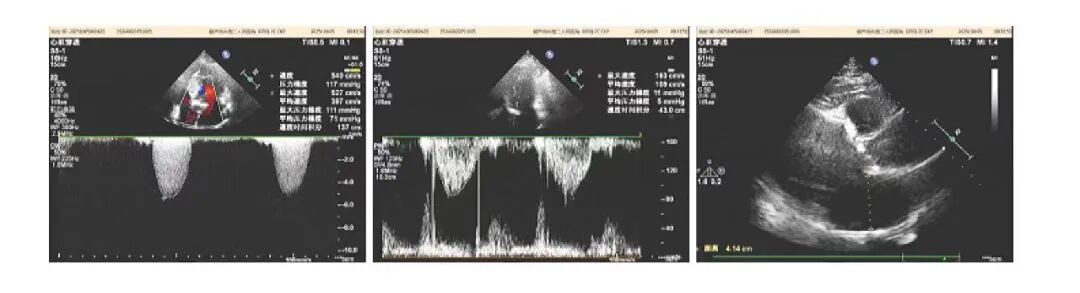

内容提要 近日,葫芦岛市第二人民医院心脏中心在常务副院长、心脏中心主任张占修的带领下,联合辽宁省人民医院副院长、著名心血管专家栾波教授,成功为一例病情复杂危重的高龄心脏疾病患者,实施了经导管主动脉瓣植入术(TAVR)。术后患者恢复良好,标志着我中心在高危心脏瓣膜病微创介入治疗领域取得又一重要突破,让本地患者在家门口即可享受与国家标准同质的顶尖技术服务。 老年男性患者,自述心脏病史长达二十年,病情极为复杂。患者曾因心肌梗死先后植入7枚支架。近期胸痛、胸闷、气短症状反复发作,检查发现主动脉瓣重度狭窄,生命健康受到严重威胁。 术前超声及诊断 面对患者复杂的心脏病史,张占修院长迅速组织多学科会诊,联合心脏血管外科李寒教授、血管介入科田明主任等专家深入评估,审慎研判传统开胸手术的高风险性,最终决策采用微创TAVR技术,以最小创伤化解危机。 经导管主动脉瓣植入术(TAVR)是心脏介入领域的一项革命性技术。它通过血管穿刺路径,将压缩的人工瓣膜输送至心脏病变部位并释放,从而替代原有病变瓣膜的功能。该技术具有创伤小、无需开胸、心脏不停跳、术后恢复快等优势,尤其适用于高龄、高危及不能耐受传统外科手术的患者。 手术当日,张占修院长团队携手辽宁省人民医院副院长栾波教授共同实施手术。术中以右侧股动脉为主要操作通路,在数字减影血管造影(DSA)的实时透视引导下,团队精准完成了导管导丝跨主动脉瓣操作,建立稳定手术轨道。依据术前精细的CT影像测量与术中造影结果,选择了尺寸最匹配的人工主动脉瓣膜,并输送至预定位置。辅以临时起搏器快速起搏以暂时阻断血流,精准完成人工瓣膜的扩张释放。术中影像显示,瓣膜支架展开完全,位置理想,植入即刻效果显著。术后患者血流动力学迅速趋于稳定,安返心脏重症监护室(CCU)。 术后复诊超声 术后患者生命体征平稳,在心脏中心医护团队的精心照护下恢复顺利。术后一月复查心脏超声显示,人工瓣膜位置固定良好,功能完善,未见瓣周漏,主动脉瓣前向血流明显改善。困扰患者多年的胸痛、胸闷、气短等症状完全消失,心功能及生活质量得到了质的提升。此次手术的成功,充分体现了TAVR技术对于复杂高危患者的救治价值。 葫芦岛市第二人民医院心脏中心始终秉承“以患者为中心”的服务理念,在心血管疾病治疗领域持续深耕,不断实现技术突破。近年来,中心在不断提升自身核心技术水平的同时,积极构建高水平医疗协作网络,与北京安贞医院、北京阜外医院、北京大学人民医院、辽宁省人民医院等国内多家知名三甲医院建立了长期、深入的技术合作关系。通过定期邀请国内顶尖专家来院手术、会诊、授课,以及选派骨干医师赴名院进修学习,实现了技术、理念与资源的同步更新。 这种“引进来、走出去”的开放模式,确保了中心始终紧跟国内外诊疗前沿进展,将最先进的技术和诊疗方案引入滨城,让以往需要远赴北上广的疑难、危重心脏疾病患者,在本地就能得到国家级标准的诊断与救治,为滨城百姓的心脏健康筑起了一道坚实、可靠的技术屏障。 特聘著名专家 栾波 医学博士 主任医师 博士研究生导师 ·辽宁省人民医院副院长 ·中华医学会心血管病学分会第十二届委员会委员 ·辽宁省心血管病预防与控制专业第三届委员会主任委员 ·辽宁省医学会心血管病分会第十届委员会副主任委员 专业特色:擅长危重冠心病及结构性心脏病介入治疗。率先完成东北首例冠状动脉“一站式”杂交手术、左心室辅助复杂PCI术、经皮主动脉瓣置换术,二尖瓣钳夹术等。特别针对复杂高危冠脉介入治疗,提出多种优化及创新方案,显著提高了手术成功率及安全性。主持国家级、辽宁省、市级课题9项,荣获辽宁科技进步奖3次,辽宁医学科技进步奖1次,辽宁医疗成果奖1次, 中国人民解放军医疗成果奖4次等,参编中国专家共识6篇,发表SCI等论文近50篇,著作8部。 院内著名专家 张占修 主任医师 教授 ·葫芦岛市第二人民医院常务副院长、心脏中心主任 ·中国健康管理协会心肺健康专业委员会常务委员 ·中国老年保健协会心血管专业委员会常务委员 ·辽宁省基层卫生协会胸痛中心建设专业委员会副主任委员 ·葫芦岛脑心同治专业委员会主任委员 ·葫芦岛市心电生理与起搏专业委员会主任委员 ·葫芦岛市心血管专业委员会副主任委员 学术荣誉:主编参编论著4部,主持参加国家省部级课题多项,发表论文30余篇。近年来相继组建了葫芦岛市心电生理与起搏学专业委员会、葫芦岛市脑心同治专业委员会;成立葫芦岛市第二人民医院专家工作站、葫芦岛市心脏病研究所、葫芦岛市首家心脏外科以及辽西地区首家心脏专科门急诊。 专业特色:在冠心病介入诊断和治疗、周围血管病介入治疗、永久起搏器安置术及顽固性心衰、高血压病、心律失常药物及射频消融治疗等方面取得了突出成绩。尤其在急诊介入救治急危急性心梗、复杂冠脉病变、左主干病变、慢性完全闭塞病变及支架内再狭窄的介入治疗方面有丰富经验和娴熟技术,多项新业务及技术填补本地区空白。 李寒 医学博士 主任医师 教授 ·葫芦岛市第二人民医院心脏中心副主任、心脏血管外科著名专家 ·原解放军总医院(301)第六医学中心心外科主任、北京中医药大学东直门医院心外科主任 ·北京医学会心血管外科分会委员 ·全军胸心血管外科学会青年委员 ·国家药品食品监督管理局医疗器械评审专家 ·北京转化医学会心外科分会常委 ·中国民族卫生医药学会心脏分会委员 专业特色:第三军医大学医学博士,从事心脏大血管外科30余年,擅长冠心病、瓣膜性心脏病、先天性心脏病、心脏肿瘤以及大血管病等心脏外科高难手术,包括:冠脉搭桥、瓣膜修复、置换,先心病矫治,主动脉夹层、动脉瘤外科手术,心脏肿瘤,外科手术中射频消融治疗心房颤动等,均在国内属于先进水平。 学术荣誉:长期致力于复杂心脏大血管外科治疗工作,参与偏远地区先心病患儿救治近4千例,并在国内开展了多项领先及高难技术,如冠状动脉旁路移植术中干细胞移植,干细胞移植治疗右室型心肌病、先心病合并重度肺动脉高压的诊断性治疗等。发表论文二十余篇,获得军队医疗成果奖两项。 田明 主治医师 ·葫芦岛市第二人民医院血管介入科副主任 ·中国医药教育协会中西医结合心血管专业委员会委员 ·葫芦岛市慢性创面修复外科分会委员 ·葫芦岛市心血管病分会委员 ·葫芦岛市心电生理与起搏专业委员会委员 ·辽宁省中西医结合学会介入心脏病学专业委员会委员 专业特色:冠心病复杂病变介入治疗、肥厚型梗阻性心肌病化学消融、下肢动脉硬化闭塞症、下肢静脉血栓、颈动脉狭窄、锁骨下动脉盗血综合征、肾动脉狭窄等外周血管疾病介入治疗、高血压、心衰、心肌炎等心血管疾病诊疗。